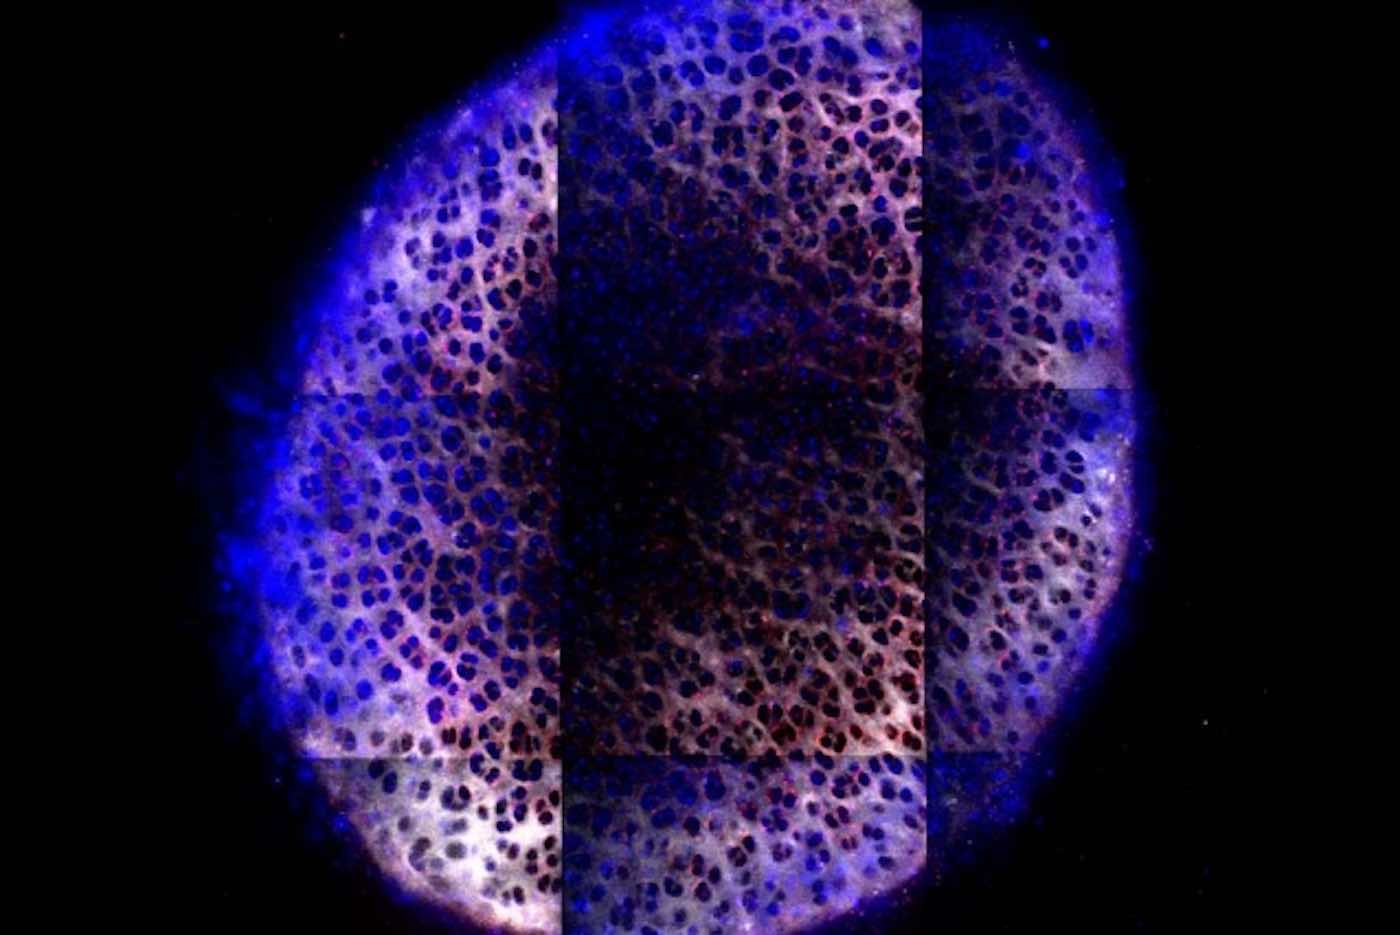

The sphere-shaped molecule they came up with contains many branched structures called dendrimers that branch from a central core. The molecule has a positive charge at the tip of each of its branches, which helps it bind to the negatively charged cartilage. Some of those charges can be replaced with a short flexible, water-loving polymer, known as PEG, that can swing around on the surface and partially cover the positive charge. Molecules of IGF-1 are also attached to the surface.

When these particles are injected into a joint, they coat the surface of the cartilage and then begin diffusing through it. This is easier for them to do than it is for free IGF-1 because the spheres’ positive charges allow them to bind to cartilage and prevent them from being washed away. The charged molecules do not adhere permanently, however. Thanks to the flexible PEG chains on the surface that cover and uncover charge as they move, the molecules can briefly detach from cartilage, enabling them to move deeper into the tissue.

Cartilage in rat joints is about 100 microns thick, but the researchers also showed that their particles could penetrate chunks of cartilage up to 1 millimeter — the thickness of cartilage in a human joint.

Cure Your Friends Of Negativity By Sharing The Good News To Social Media – Photo by Brett Geiger and Jeff Wyckoff